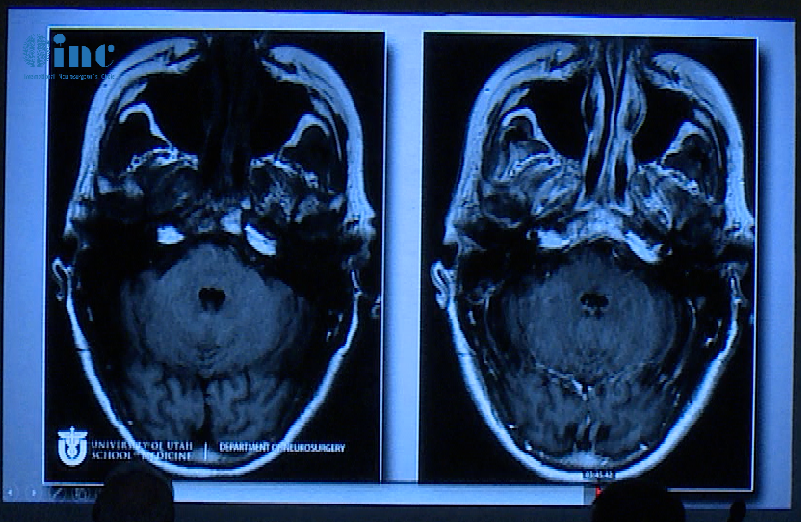

患者术前情况:62岁女性,患者35年前有垂体大腺瘤复发史,随后接受放射治疗复发性肿瘤引起的侧性眼球麻痹的进行性复视。

术后影像片子显示肿瘤切除干净: